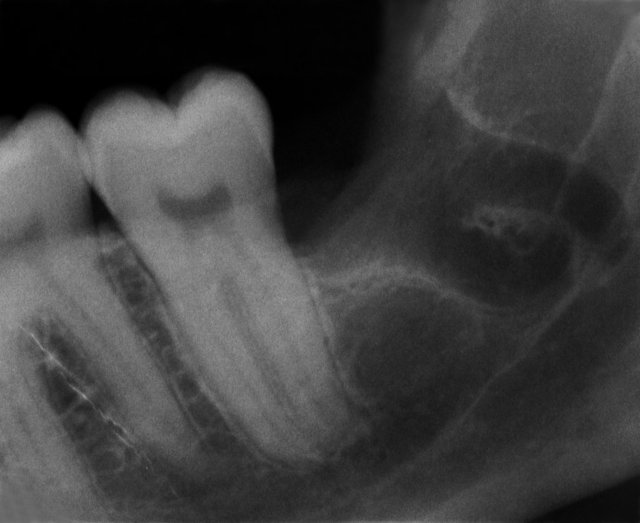

Follikuläre Zysten um die unteren beiden Weisheitszähne

3D Röntgenbild